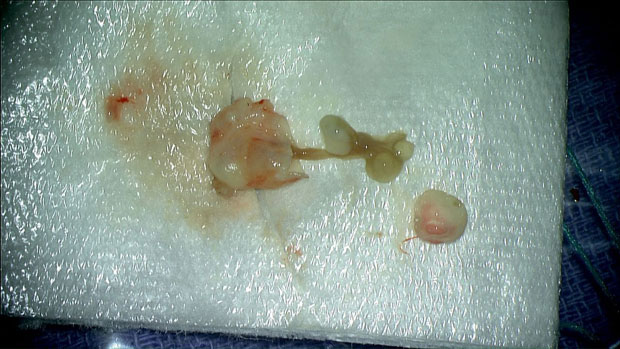

– Svi smo se čudili i pitali: Šta je ovo. Pomalo smo bili šokirani i iznenađeni izgledom – prisjeća se Rasuli za Vašington post. Hirurzi su odstranili masu, a onda je i stavili pod mikroskop i shvatili da se radi o larvi pantljičare.

Izvađena pantljičara, foto Mount Sinai Health System